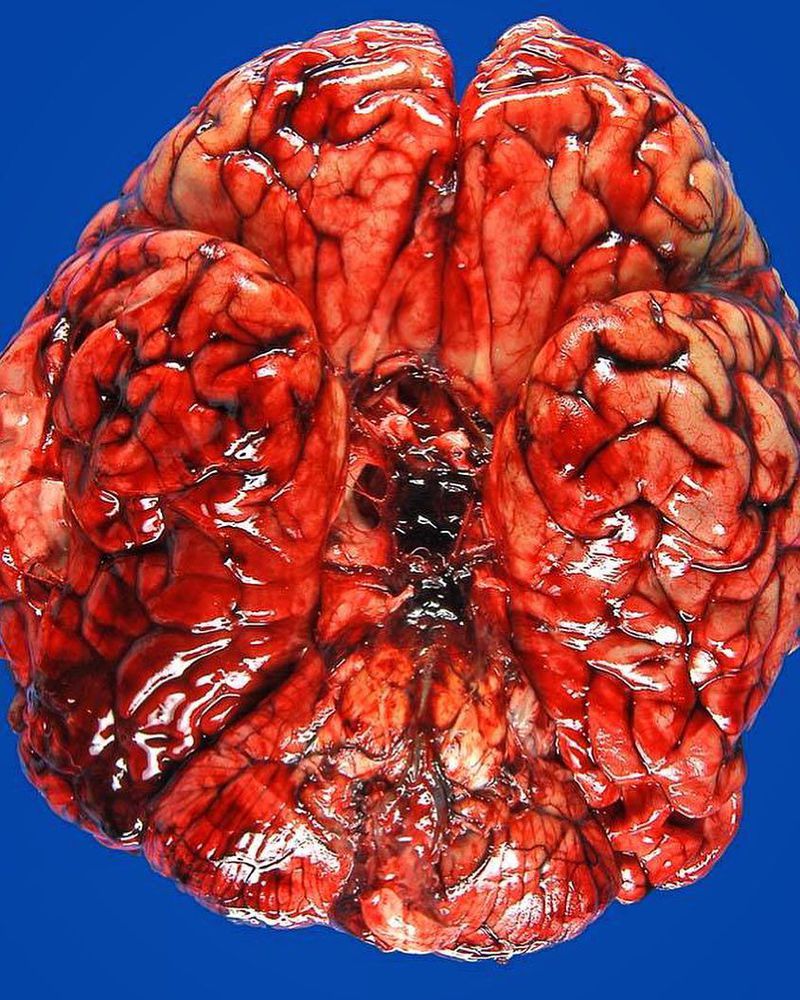

Notice the dark hematoma at the center at this brain autopsy. This happened due to extravasation of blood into the subarachnoid space between the pial and arachnoid membranes surrounding the entire brain. It occurs in various clinical contexts, the most common being head trauma. However, the familiar use of the term subarachnoid hemorrhage refers to nontraumatic (or spontaneous) hemorrhage, which usually occurs in the setting of a ruptured cerebral aneurysm (weaknesses in the wall of the arteries of the brain that enlarge and its rupture leads to severe bleeding) or arteriovenous malformation. The classic symptom is thunderclap headache ("most severe ever" headache developing over seconds to minutes), and is often described like being "kicked in the head". Other symptoms may be vomiting, seizures, photophobia, loss of consciousness and meningism, but these are significantly less common and non-specific. Due to its acute onset, it is a medical emergency which can lead to death or severe disability even if recognized and treated in an early stage. Surgical treatment to prevent rebleeding includes clipping the ruptured aneurysm or endovascular treatment (ie, coiling).